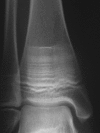

Evaluation of the child with fractures is challenging, as no clear guidelines exist to distinguish traumatic from pathological fractures. Although most fractures in childhood are benign, recurrent fractures may be associated with a wide variety of primary skeletal diseases as well as secondary causes, necessitating a careful history and physical exam to guide the evaluation. There is no "gold standard" for the evaluation and treatment of children with fractures and low bone mineral density (BMD); therefore, the diagnosis of osteoporosis in a pediatric patient should be made using a combination of clinical and radiographic features. Interpretation of bone densitometry in growing patients presents a unique set of challenges because areal BMD measured by dual-energy x-ray absorptiometry depends on multiple dynamic variables. Interpretation of pediatric dual-energy x-ray absorptiometry should be based on Z-scores (sd scores compared to age, sex, and ethnicity-matched controls), using normative databases specific to the brand of densitometer and the patient population. Given the skeleton's ability to recover from low BMD through modeling and remodeling, optimizing management of underlying conditions leading to bone fragility is the initial step. Conservative measures including calcium and vitamin D supplementation and weight-bearing physical activity are important interventions that should not be overlooked. The use of bisphosphonates in children and adolescents is controversial due to lack of long-term efficacy and safety data and should be limited to clinical trials and compassionate therapy in children with significantly compromised quality of life. Close monitoring is required, and further study is necessary to assess their long-term safety and efficacy in children.